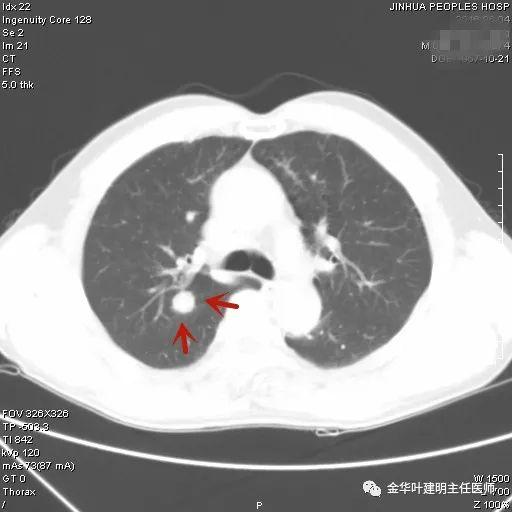

上图示典型的肺内淋巴结影像。靠近胸膜,高密度,三角形工多边形,相对比较孤立,周围没有炎性渗出或卫星灶,邻近胸膜(包括叶间胸膜)但无胸膜牵拉凹陷。